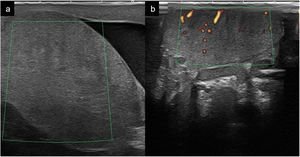

Cuando hay más de 5 microcalcificaciones presentes en una imagen del testículo, esto se denomina microlitiasis testicular. En la ecografía se ven como focos hiperecogénicos de 1 a 3mm sin sombra acústica posterior (Fig. 4). El hallazgo ecográfico de microlitiasis testiculares se encuentra en aproximadamente el 5% de los varones entre los 18 y 35 años. A pesar de múltiples estudios, la relación con el cáncer testicular no está claramente definida.

VaricoceleSe define como la dilatación de la vena testicular y del plexo venoso pampiniforme dentro del cordón espermático. Dentro de la historia clínica los pacientes presentan dolor crónico de leve intensidad. Al examen físico se convierte en la masa palpable más común del cordón espermático, siendo predominante en un gran porcentaje de varones con problemas de fertilidad. Su presentación es con mayor frecuencia en adultos jóvenes predominando en el lado izquierdo 85%, 15% bilateral. Si aparece un varicocele derecho aislado se estudiará la causa de la obstrucción del drenaje venoso buscando descartar sus múltiples afectaciones (trombosis de la vena renal derecha, masa renal o retroperitoneal y situs inverso)7,9,10,19 (Fig. 6).

Ecográficamente se visualizan imágenes tubulares, anecogénicas o hipoecogénicas con trayecto tortuoso, con un diámetro mayor de 2 a 3mm, que serán más evidentes al realizar maniobras de Valsalva o en la bipedestación. El uso de ecografía Doppler color nos ayudará a confirmar el diagnóstico al visualizar la existencia de flujo venoso. Con la técnica de Doppler pulsado se visualizará flujo retrógrado durante más de 2s durante la maniobra de Valsalva10,11,24.

La ecografía es poco específica en el modo B, cuando se detectan alteraciones en la ecogenicidad es en los casos de torsión avanzada, en los que puede haber una ecogenicidad heterogénea con áreas hipoecogénicas debido a la congestión, edema e infarto, así como un claro aumento de tamaño del testículo afectado. Es imprescindible utilizar el modo Doppler para el diagnóstico. Inicialmente existe una ausencia de flujo venoso y posteriormente también arterial en el testículo afecto al compararlo con el contralateral (Fig. 8). Ha de confirmarse la presencia de flujo en las venas y en las arterias intratesticulares mediante la técnica Doppler espectral (pulsado). Respecto al cordón espermático se puede visualizar el giro o tirabuzón del cordón, conocido como «whirlpool sign». Es muy específico de torsión testicular y se manifiesta como una masa con forma de espiral de localización posterosuperior al testículo con ausencia de flujo o escaso flujo en los casos de torsión intermitente (vídeo 4). En los casos de resolución espontánea se puede ver un flujo intratesticular muy aumentado debido a la llamada fase de reperfusión1,9,28,30.